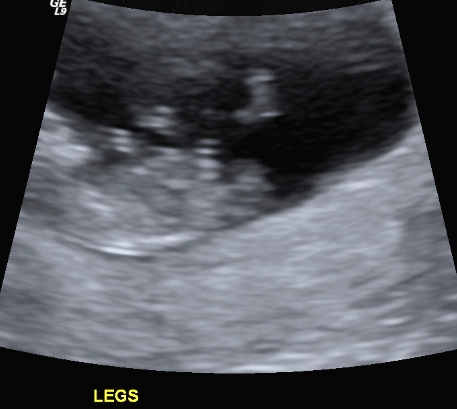

I finally managed to get hold of my u/s disc and have selected a few of the pics I think could have a nub in them (I'm still pretty hopeless at working out nubs).

There is only 1 pic from my 19 week scan that even comes remotely close to the bottom region and I'm pretty sure it is not a potty shot, just of legs from above I think??? (second last pic...biggest one)...I'm a little p'd off with the tech as I asked him to get a pic for me and he obviously didn't.